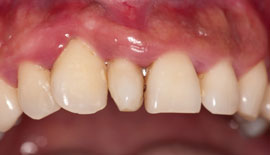

The image depicted here is one of what is termed a supernumerary tooth. In this case, it is called a mesiodens (see Figure 1). Supernumerary teeth are in excess of the normal number of teeth, and they are further classified according to their location.

A mesiodens is a supernumerary tooth in the maxillary anterior incisor region. If the supernumerary tooth were found in the posterior region it would be termed a distomolar or distodens (4th molar). If the tooth happens to be found lingually or buccally, the term paramolar is used (see Figure 2). Developmental alterations can occur affecting the number of teeth, the size of teeth, the shape of teeth, and the structure of teeth.

The mesiodens interfere with eruption and cause other alignment problems with the existing teeth. Only a small portion of supernumerary teeth eventually erupts (approximately 25%) and the pattern of eruption is usually the first indication of a problem in the case of mesiodens. Because of the concern in eruption patterns, the dental professional usually orders radiographs to assess any problems that may be unseen clinically. Radiographs provide some assistance, but are often vague because of primary teeth obstruction.